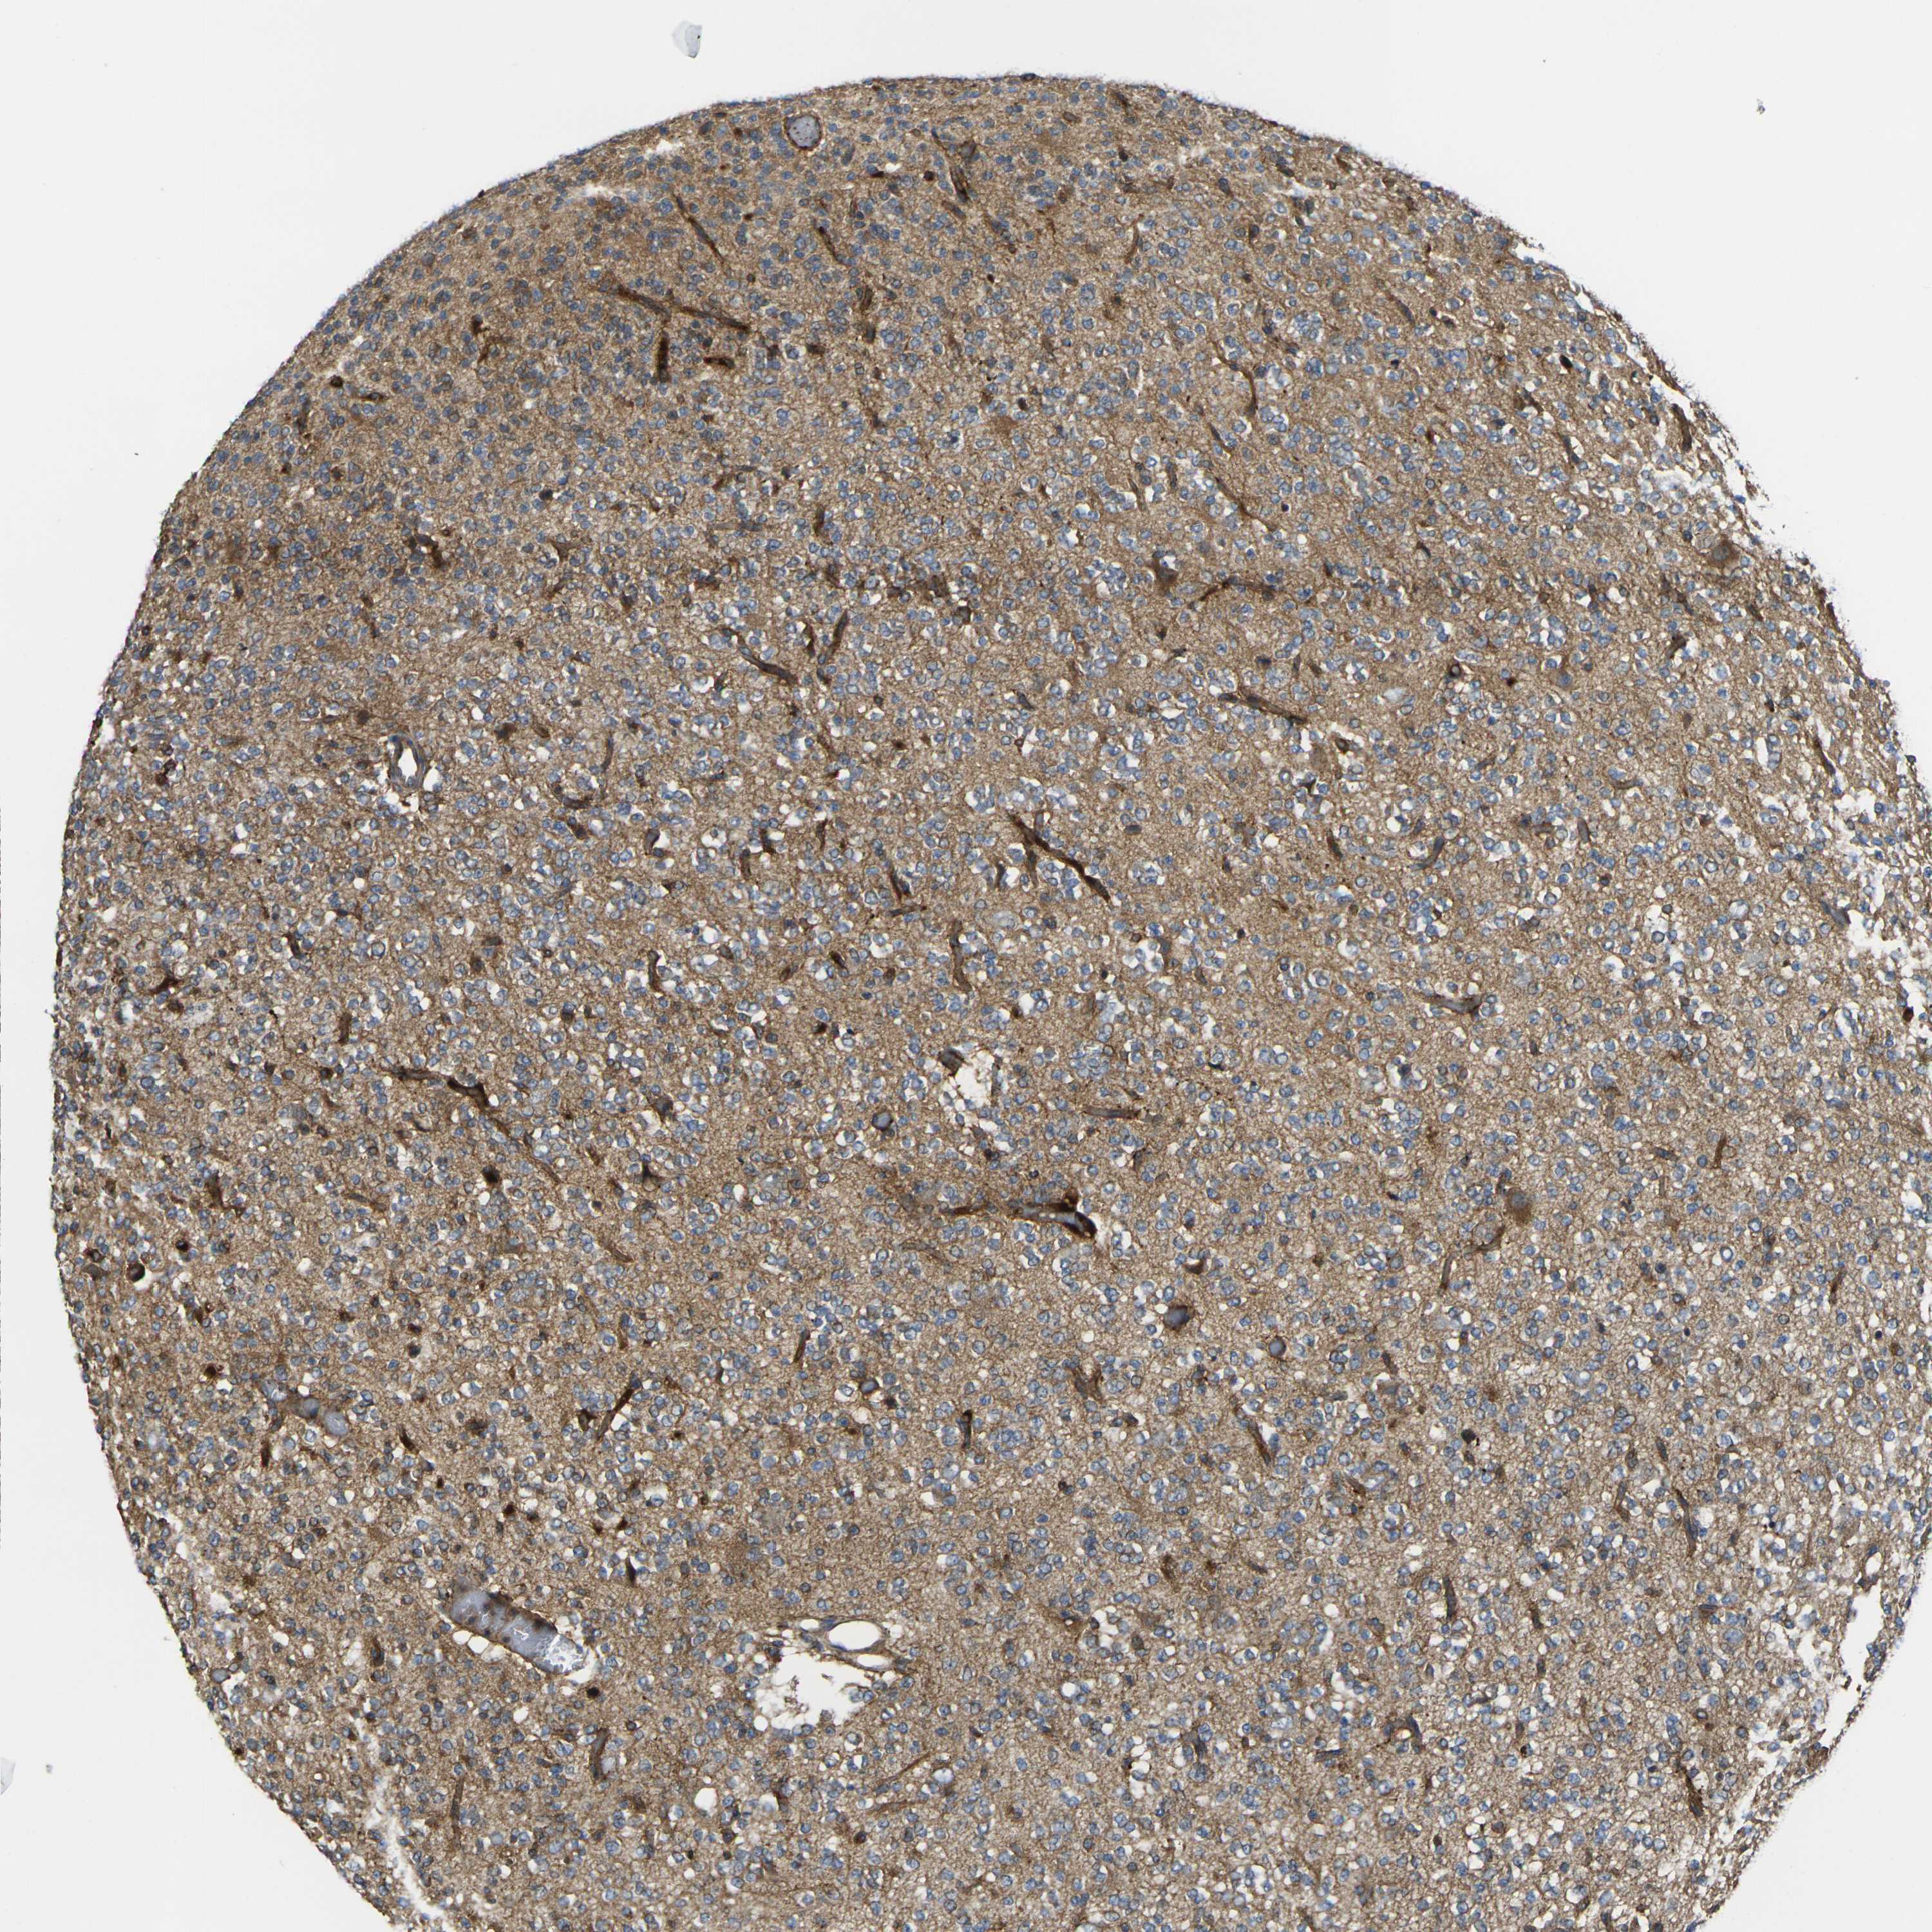

GLIOMA - Protein expressioni

A mouse-over function shows sample information and annotation data. Click on an image to view it in a full screen mode. Samples can be filtered based on level of antibody staining by selecting one or several of the following categories: high, medium, low and not detected. The assay and annotation is described here.

Note that samples used for immunohistochemistry by the Human Protein Atlas do not correspond to samples in the TCGA dataset.

Antibody stainingi

Antibody staining in the annotated cell types in the current human tissue is reported as not detected, low, medium, or high, based on conventional immunohistochemistry profiling in selected tissues. This score is based on the combination of the staining intensity and fraction of stained cells.

Each image is clickable and will lead to virtual microscopy that enables deeper exploration of all samples and also displays staining intensity scores, fraction scores and subcellular localization as well as patient and tissue information for each sample.

Antibody CAB013008

Staining

High

Medium

Low

Not detected

Intensity

Strong

Moderate

Weak

Negative

Quantity

>75%

75%-25%

<25%

None

Location

Nuclear

Cytoplasmic/membranous

Cytoplasmic/membranous,nuclear

Glioma, malignant, High grade

Glioma, malignant, Low grade